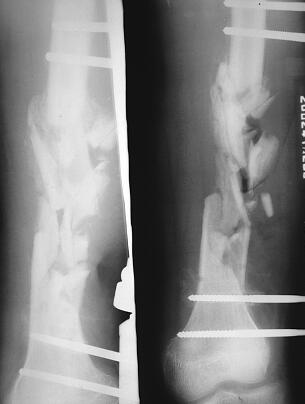

患者,男,19岁。因“撞伤右股骨骨折术后窦道流脓4个月余”于2002年6月4日入院。于2002年1月28日骑摩托车时撞伤右大腿,当时局部肿痛较重,畸形,大腿前侧有一3cm挫裂口,其内可见游离的骨折块,活动受限,遂至当地县骨科医院就诊,拍摄X线片(图1),诊断为右侧股骨开放性骨折,行清创、切开复位支架固定术(图2),术后2周时伤口处红肿,向外流脓;细菌培养为肺炎克雷伯菌生长,给予二次清创、持续冲洗引流,使用抗生素6周后,切口愈合,血常规正常,常规出院。骨折固定术后2个月时,局部再次红肿,发热,跳痛,切口旁出现2个窦道,有脓性物外溢,细菌培养为耐药性金黄葡萄球菌、肺炎克雷伯菌生长,再次住院,静输敏感抗生素4周,窦道间断性流脓,间有碎骨片溢出。现因右大腿窦道流脓量大,故而转诊我院。

图2 第1次手术X线片